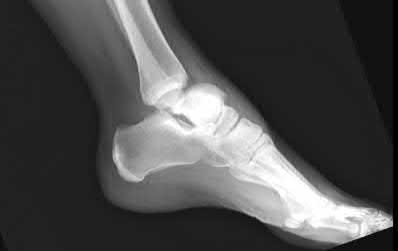

A 28-year-old male sustains a severe hyper-dorsiflexion injury to his ankle in a motor vehicle accident, resulting in a Hawkins Type III talar neck fracture. Which of the following arteries provides the predominant blood supply to the body of the talus, placing it at significant risk for avascular necrosis in this injury?

Correct Answer: Artery of the tarsal canal

Explanation:

The artery of the tarsal canal, which is a branch of the posterior tibial artery, provides the dominant blood supply to the talar body. In a Hawkins Type III fracture (talar neck fracture with subtalar and tibiotalar dislocation), the blood supply from the artery of the tarsal canal, the artery of the sinus tarsi, and capsular vessels are disrupted, leading to an avascular necrosis (AVN) rate approaching 100%.